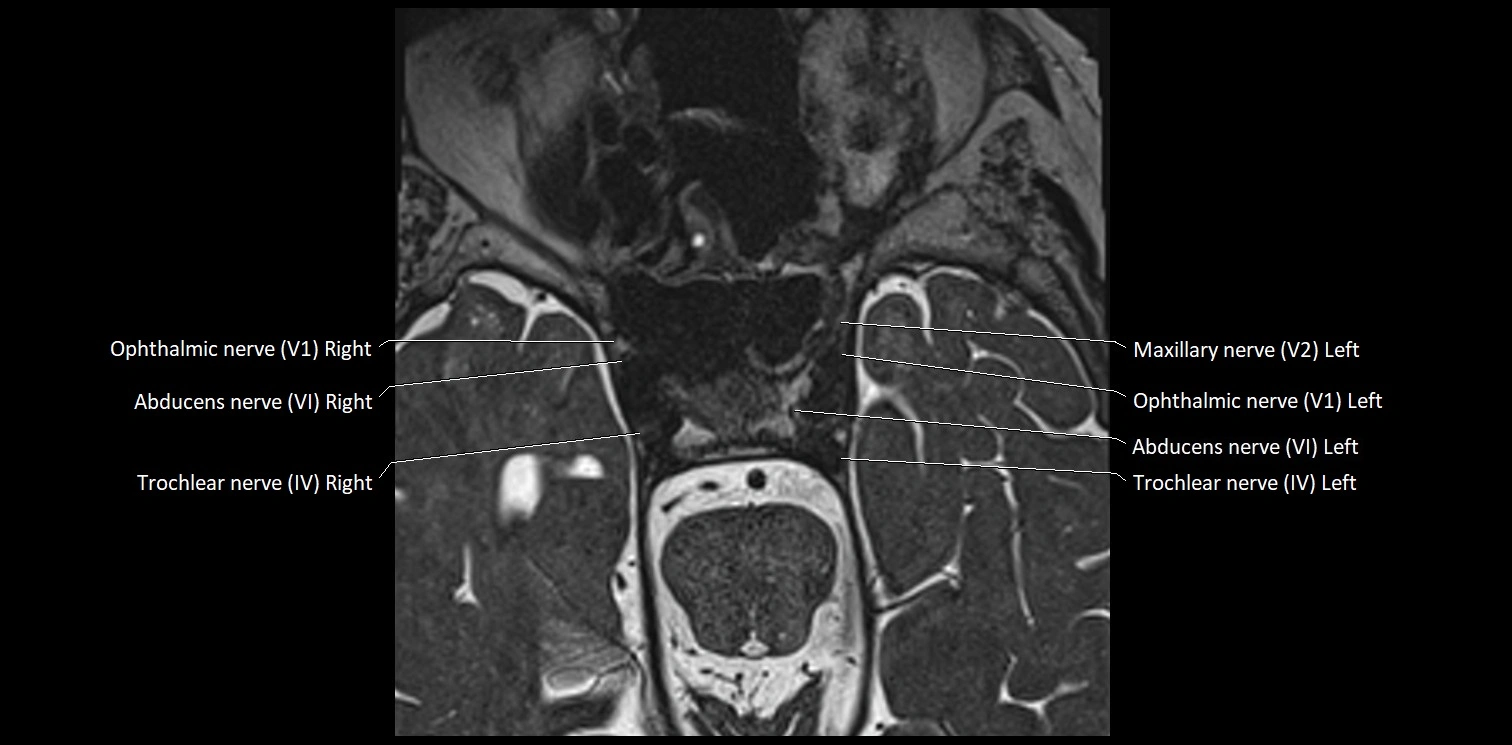

MRI Appearance

• The abducens nerve is a small, thin, linear structure

• Best visualized on high-resolution T2-weighted 3D MRI sequences (e.g., FIESTA or CISS)

• Seen as a hypointense (dark) line running from the brainstem at the pontomedullary junction, traversing the prepontine cistern, and entering Dorello’s canal under the petrosphenoidal ligament, then into the cavernous sinus, and finally the orbit

• May be challenging to visualize in standard MRI due to its small size

• Pathology may be inferred by absence, displacement, or enhancement of the nerve